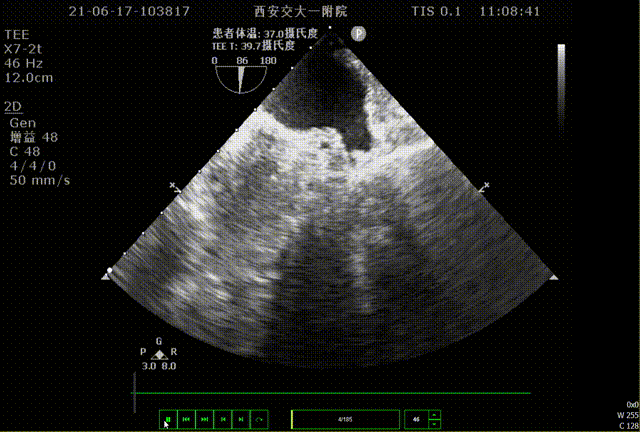

术前TEE评估

术前排除左心耳血栓,左心耳可能呈反鸡翅型,心耳偏小,梳状肌发达。

0°TEE

86°TEE

该患者左心耳开口较小,呈反鸡翅型,开口处即反折,同时内部梳状肌发达,且深度较浅,因此手术难度偏大,术前安排进一步CT评估以协助制定手术策略。